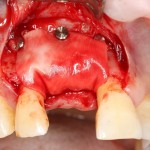

В этом случае остеопластика делается отдельной процедурой. Ее принципы точно те же, но уже без импланта. Например:

Имплантировать в таких условиях — заведомо обрекать себя на хреновый, с точки зрения эстетики и функциональности, результат. Поэтому первым этапом проводим остеопластику. Объем небольшой, использовать в таких объемах костный блок не очень рационально. Воспользуемся аутокостной стружкой и мембраной.

Сначала фиксируется BioGide. Это легко:

Затем укладывается и конфигурируется аутокостная стружка:

Если после этого BioGide намочить физраствором, им легко укрыть получившийся объем:

Для надежности можно зафиксировать пинами: